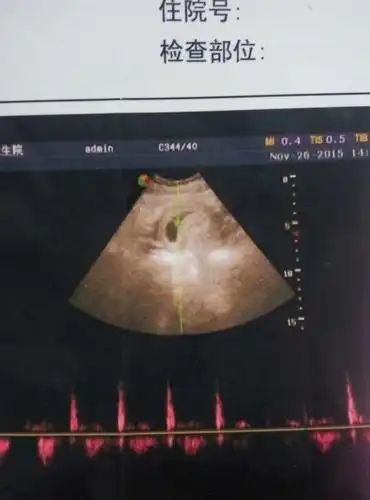

在线的宝妈帮忙看看50天的孕囊4.2/2.